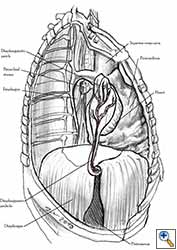

Medium and large-sized (Figures 1a, 1b) defects generally result after pneumonectomy for advanced central lung tumours which invade the pericardium (T3 invading pericardium), thus requiring reconstruction (Figure 1c). To achieve a curative resection, negative pericardial resection margins must be obtained and checked microscopically. More invasive tumours (T4 invading cardiac structures) require partial atrial resection and pericardiectomy associated with pneumonectomy.

|

| Figure 1c: Intraoperative aspect of pericardioplasty with Marlex mesh after right completion pneumonectomy with partial pericardiectomy. |

Pericardioplasty is also indicated for pericardial defects resulted after harvesting the pericardium to cover the bronchial stump after pneumonectomy (Figures 2a, 2b) [3]. Similarly, other defects that result after harvesting a pericardial graft for various purposes may need prophylactic reconstruction.

Video 1 depicts a pericardial reconstruction with Marlex after a right completion pneumonectomy with pericardiectomy for lung adenocarcinoma (see also Figure 1). The technique of pericardial reconstruction after the resection of invasive mediastinal tumours is illustrated in Figures 8a-c). Video 2 depicts a pericardial reconstruction with Mersilene mesh after the resection of a malignant thymoma invading the anterior pericardium (see also Figure 4b). The technique of right pericardial reconstruction after extrapleural pneumonectomy is illustrated in Figures 9a and 9b). Video 3 depicts a pericardial reconstruction using Gore-Tex Dual Mesh after a left extrapleural pneumonectomy (see also Figure 3). Care must be taken to prevent constriction (Figure 10).